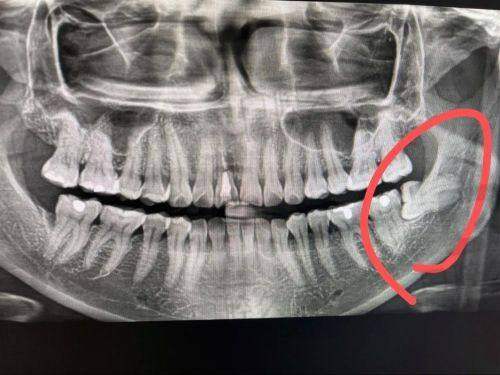

精细诊断技术:医院会通过全景片等精良设备对智齿的具体情况进行详细评估,医生能够清晰地了解智齿的位置、生长方向、与周围组织的关系等,从而制定出更加精细的拔牙方案。这样可以有效避免在拔牙过程中对周围牙齿、神经和血管造成不必要的损伤。